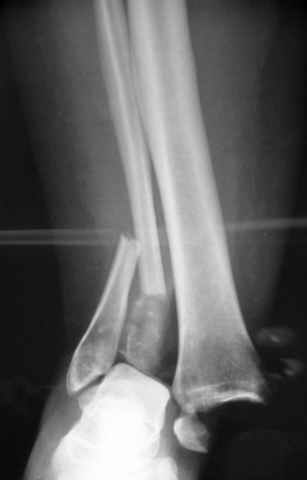

Еще, кстати, о фиксации лодыжки, если уж непременно хочется ее отдельно стабилизировать - при таком характере перелома замечательно должен сработать предложенный проф. Лазаревым с соратниками способ фиксации напряженной V-образной спицей. Опять же, открытая репозиция не нужна, мы делаем непрямую репозицию именно аппаратом. В приложении пример, там перелом малоберцовой куда менее поперечный, чем в данном случае, но все равно получилось закрыто без пластинки.

I can't realize why plate fibula separately if anyway external fixator including the foot is planned, i.e. one may insert wires to the talus, calcaneus, lateral malleolus and anywhere else. Plating looks reasonable if only temporary ex-fix is planned, but in the case it will be definitive.

A propos fibular fixation if one is eager to stabilize it separately. In the fracture pattern a way of closed fixation by V-shaped stressed wire (advanced by colleagues from Moscow, prof. Lazarev A.F. et al.) must be excellent. We use indirect closed reduction by the external fixator. Example attached, that fibular fracture is even more suitable for plating but the wire did the job.